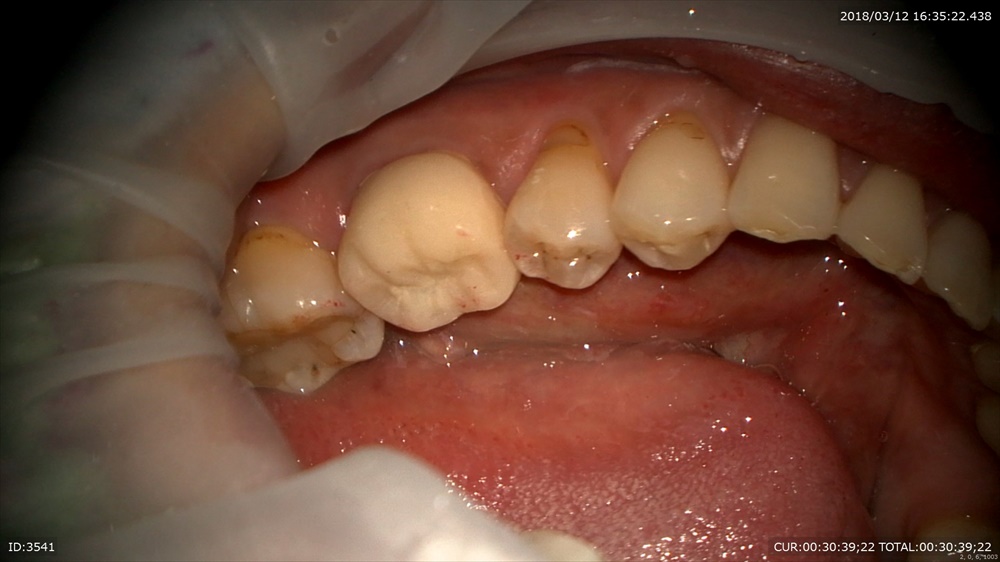

この方は根管治療が終わり土台をつけ仮歯を作成しました。

この方も根管治療は2回。

根管治療後も精密な土台と仮歯を作り細菌感染を防ぎます。

土台

仮歯を

調整

これで噛めるか試験です。

当院が治療中、仮歯を必ず入れる理由は実際使って頂いて(本物と同じ形)大丈夫か判断するからです。

次回は精密な型をとります。